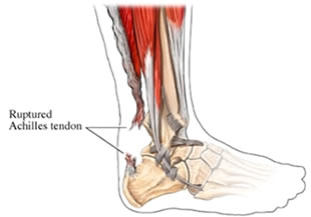

Roturas del tendón de Aquiles

Cuando

el

tendón

de

Aquiles

se

rompe

lo

hace

frecuentemente

de

forma

completa

y

brusca.

Lo

más

frecuente

es

que

el

paciente,

casi

siempre

deportista,

note

un

dolor

fuerte

y

agudo,

con

la

sensación

de

que

alguien

le

hubiera

pegado

una

patada.

A

veces

se

escucha

el

desgarro

del

tendón.

A

partir

de

ese

momento

no

se

puede

continuar

con

la actividad ni apenas caminar.